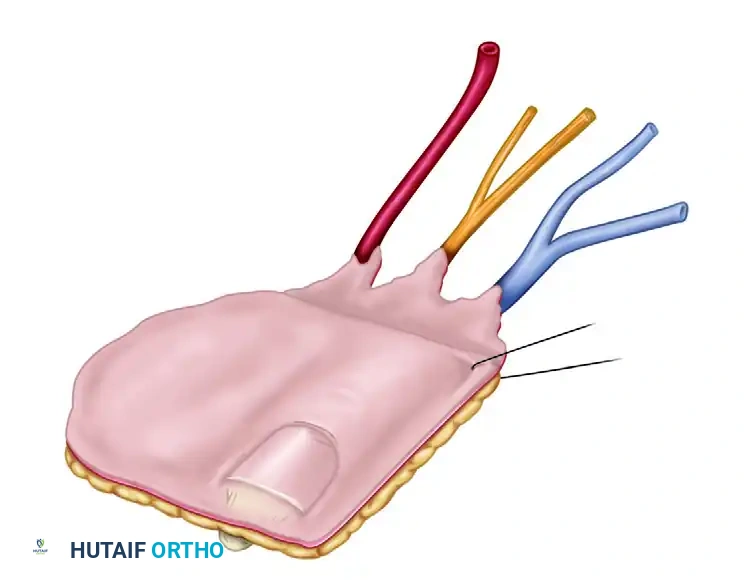

Venous Dissection

- Begin the dissection dorsally. Identify and dissect the dorsal veins draining the toe flap.

- Trace these veins proximally to the saphenous venous system.

- Cauterize small side branches meticulously to obtain maximum length for the venous pedicle.

Arterial Dissection

- Identify the first dorsal metatarsal artery (FDMA) within the first web space.

- Trace the FDMA distally to its dorsal digital branches supplying the great toe.

- If the FDMA is hypoplastic or absent, the plantar metatarsal artery must be utilized.

Neural Dissection

- Identify the deep peroneal nerve running lateral to the artery. Follow it into the toe flap and divide it proximally to secure adequate length for coaptation at the recipient site.

- Elevate the plantar surface of the flap. Leave the subcutaneous fat over the plantar surface of the toe intact to protect the underlying structures.

- Identify the lateral plantar neurovascular bundle. Mobilize it and keep it intact with the flap.

- Dissect the lateral plantar digital nerve from the common digital nerve at an appropriate proximal level.

- Identify the medial neurovascular bundle and ensure it remains completely intact with the preserved medial strip of skin.

At this stage, the flap should be completely free from the toe, tethered only by its neurovascular pedicle (the dorsal digital branches of the FDMA and the saphenous venous tributaries).